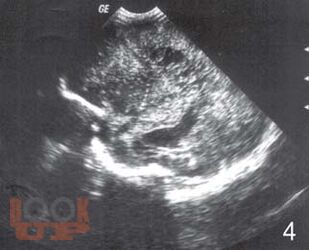

Монография посвящена вопросам ранней диагностики формирования тяжелых структурных постгипоксических изменений мозга у новорожденных детей с помощью определения в крови концентрации нейроспецифических белков, фактора роста сосудов, молекулы клеточной адгезии и маркера апоптоза в раннем периоде постнатальной адаптации. Перед педиатрами и неврологами, занимающимися новорожденными высокого риска всегда встает вопрос: разовьется ли у ребенка внутрижелудочковое кровоизлияние или перивентрикулярная лейкомаляция? Что лежит в основе таких изменений? Результаты, полученные в исследовании, позволили во многом расширить понимание патогенеза постгипоксических изменений головного мозга у новорожденных, а также выделить факторы, которые возможно применять в диагностике патологических процессов в ткани мозга как маркеры. Книга предназначена для детских неврологов, неонатологов, педиатров.